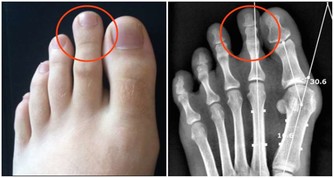

在很多男性看來,尿頻、尿急、尿不盡和眼花、牙齒脫落一樣,都是衰老的自然表現,不用擔心。然而,50

歲以上男性出現這些症狀,往往意味著良性前列腺增生症。若不及時就醫、治療,可能會出現尿瀦留、反復血尿、泌尿系統感染,甚至誘發腎積水。要想避免前列腺出現“故障”,最好的方法就是多喝水,每天要喝2000—2500毫升;不憋尿;多放鬆,保持心情愉快;洗溫水澡,緩解肌肉與前列腺緊張。